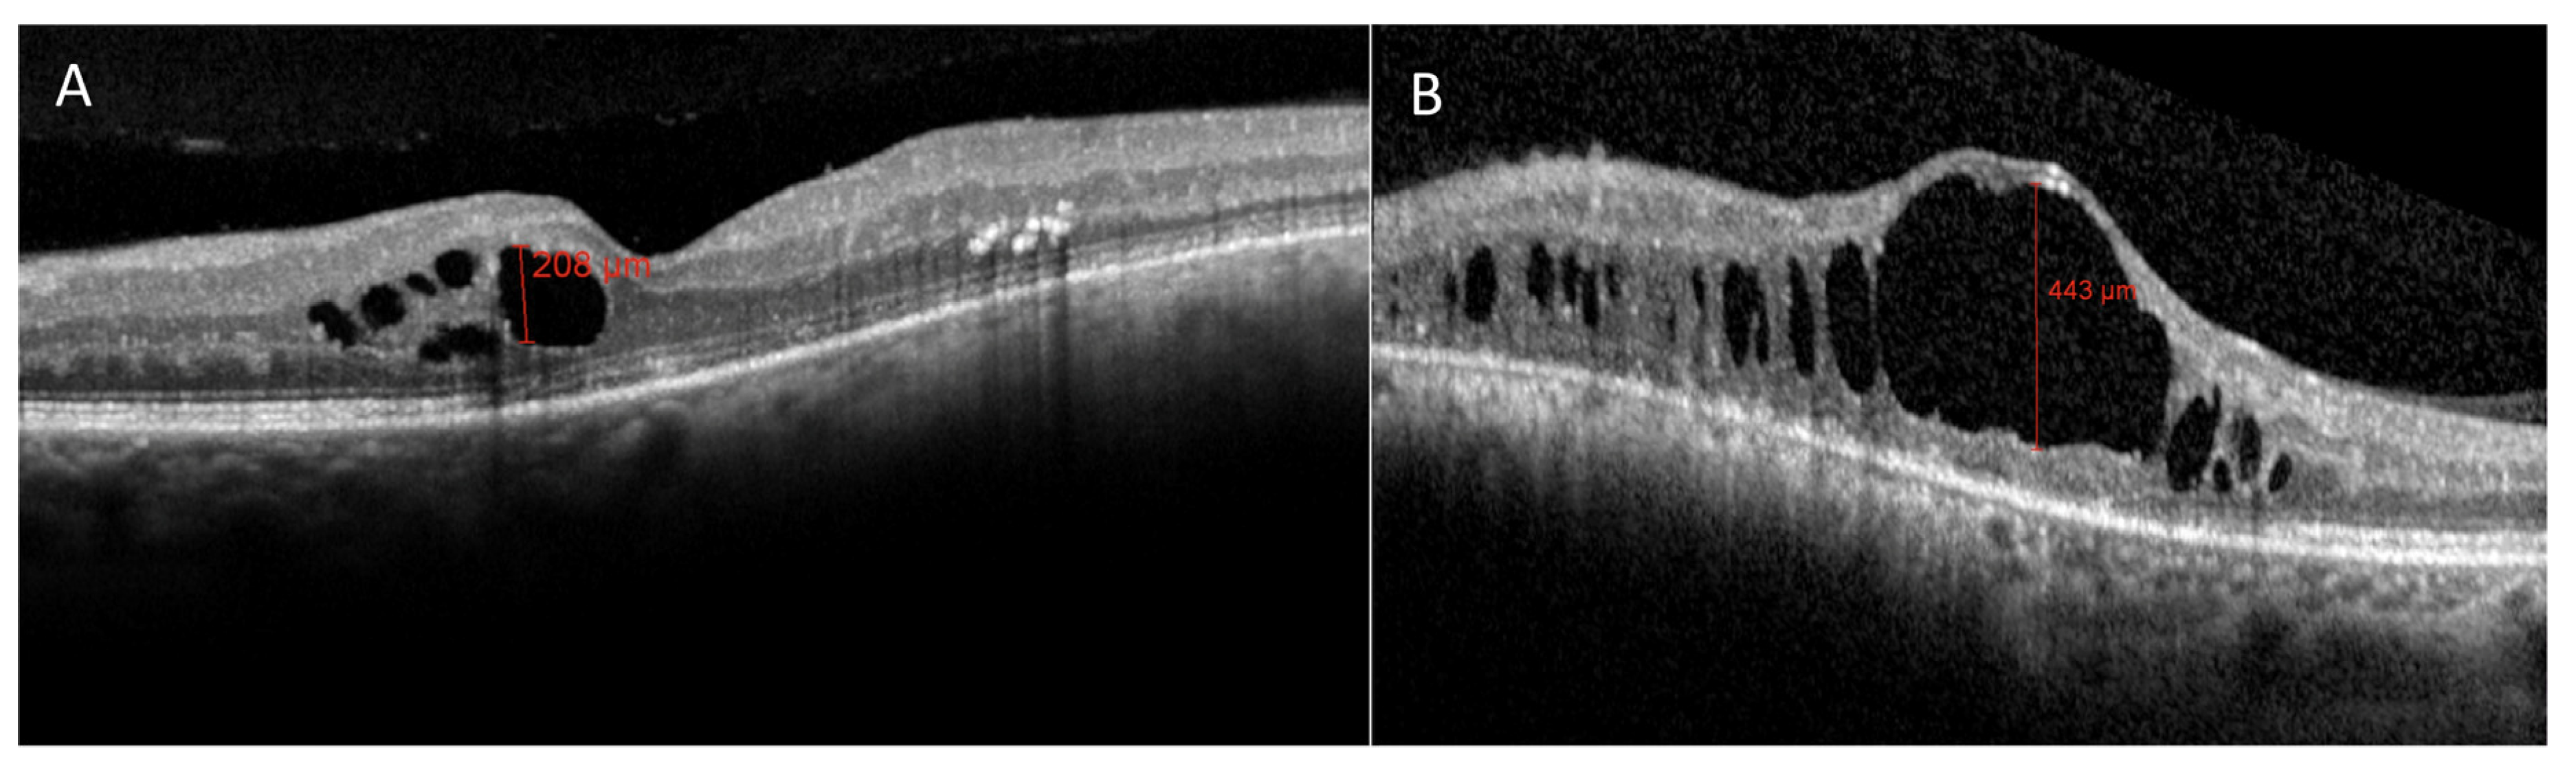

3.2. Radiation Maculopathy

- Parrozzani, R.; Midena, E.; Trainiti, S.; Londei, D.; Miglionico, G.; Annunziata, T.; Frisina, R.; Pilotto, E.; Frizziero, L. Identification and classification of macular morphologic biomarkers related to visual acuity in radiation maculopathy. Retina 2020, 40, 1419–1428. [Google Scholar] [CrossRef]